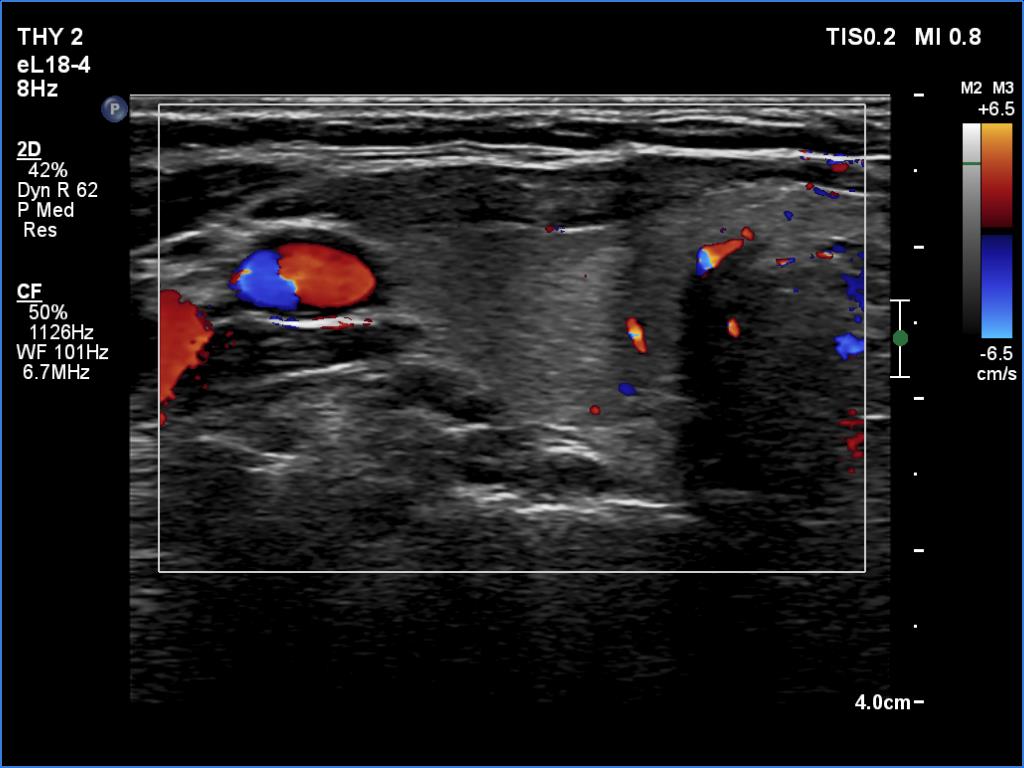

Initial examination (first row of images):

Clinical presentation: A 39-year-old woman was referred for evaluation of neck complaints lasting for more than a month. The patient had fever, neck pain. She has got two courses of antibiotics and non-steroid anti inflammatory drugs which had no effect.

Palpation: The right lobe was painful and hard while the left lobe was tender.

Laboratory examination: TSH 0.01 mIU/L, FT4 29.1 pM/L, FT3 7.45 pM/L, CRP 31.2 mg/L.

Ultrasonography: The thyroid presented with hypoechoic areas which had blurred borders. The echogenicity index was approximately 65% in the right and 20% in the left lobe. The thyroid was almost completely avascular.

Diagnosis: subacute, granulomatous de Quervain's thyroiditis.

Suggestion. Steroid therapy was suggested.